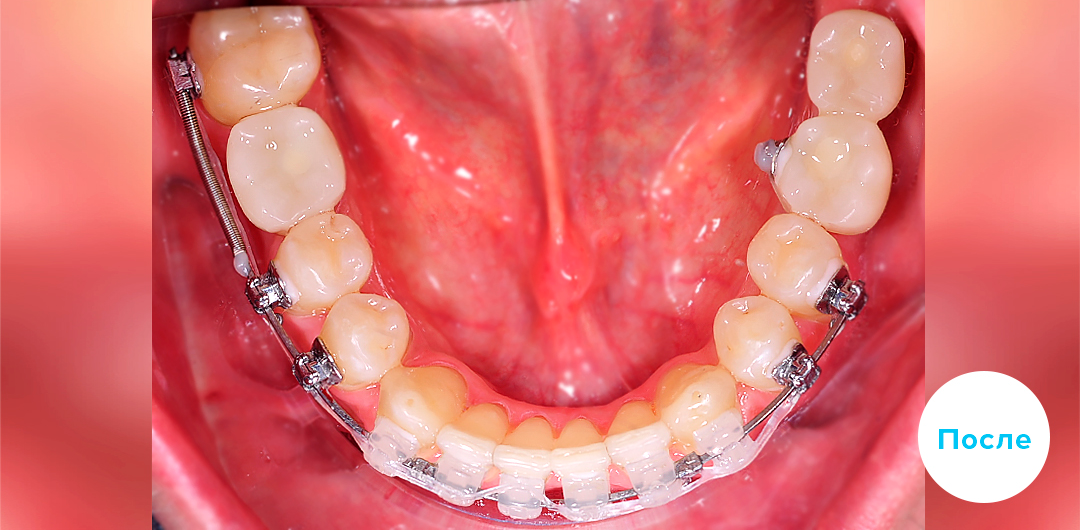

Результаты лечения